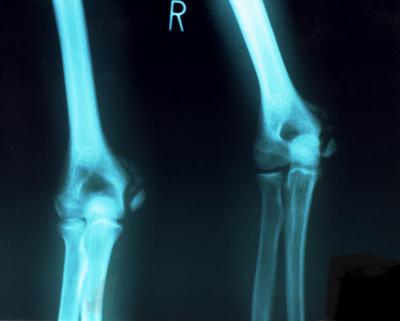

(上腕骨内顆骨折)